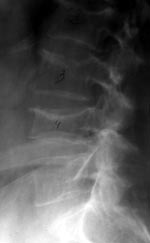

3. Задняя клиновидная деформация — уменьшение преимущественно задних отделов тел (снижение hP/hPn и некоторое увелиычение значений hА/hР и hМ/hР) (Рис. 3).

[Увеличить]

Рис. 3. Компрессионная деформация LI .